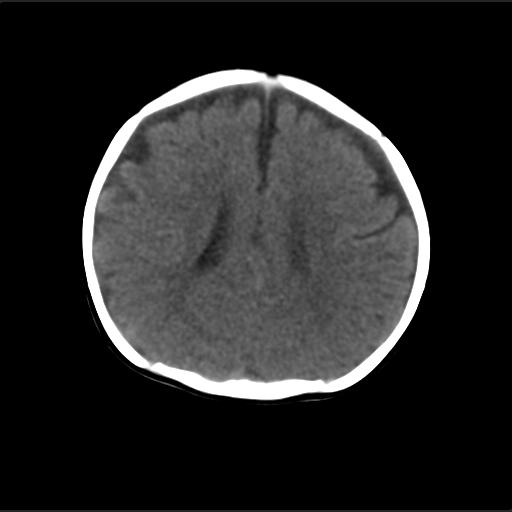

f2m出生已来可见右侧枕部见包块,质地软,无外伤史。包块处ct值16-67hu,大小约3.1x3.2cm左右。

产伤?---骨膜下血肿机化?骨折?---外部性脑积水

考虑血肿机化,外部性脑积水.

血肿机化可能性 比较大,伴双侧额颞顶部硬膜下积液。估计产伤引起